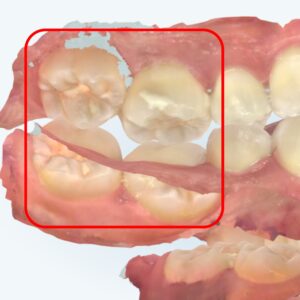

상봉역 교정치과 좁은 악궁(V-shaped arch)으로 인한 심한 총생, 어떻게 해결할까?

사람을 처음 만나는 자리에서 미소를 지으면 호감도가 높아진다는 것은 누구나 아는 사실입니다.😊 하지만 치열이 콤플렉스인 경우, 앞니를 드러내며 환하게 웃는 것 자체가 큰 부담이 될 수 있습니다. 23.11.17 ➡ 특히…